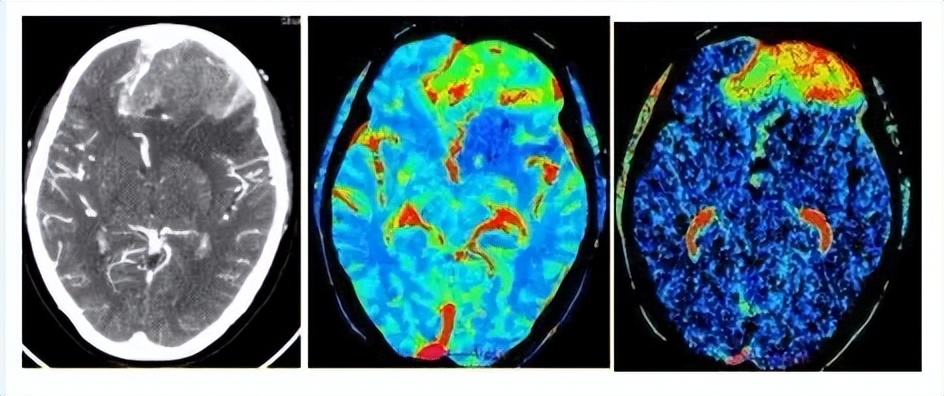

放射医学主要研究电离辐射对人体的作用、损伤与修复等方面的基本知识和技能,进行放射诊断、放射治疗、放射损伤的修复等。例如:使用X光机、CT等进行放射诊断,利用放射线进行肿瘤治疗,辐射损害的诊断与治疗等。